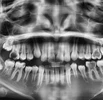

ألم الأسنان

تسوس الأسنان

فقدان الأسنان

اعوجاج الأسنان

أمراض الأسنان واللثة